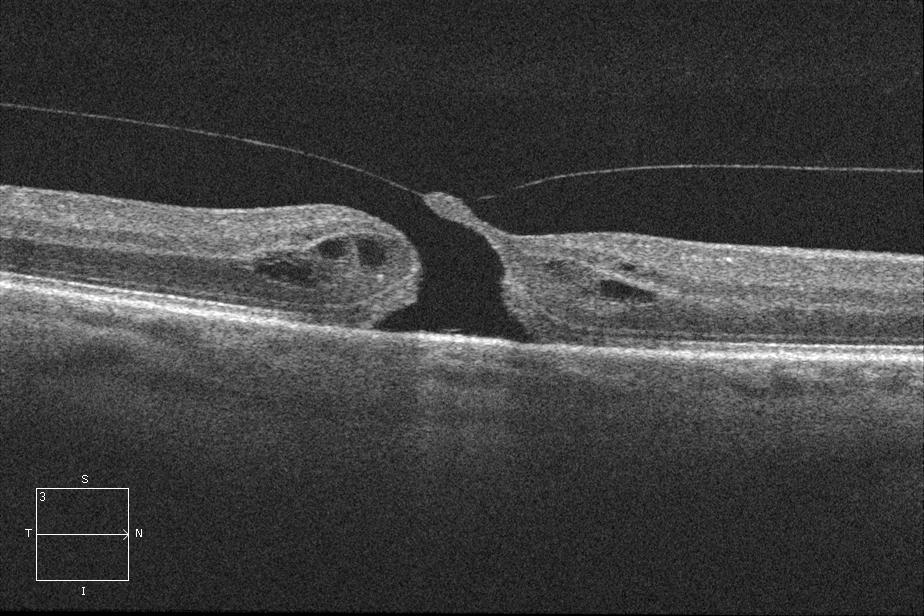

Optical coherence tomography (OCT) allows noninvasive visualization and imaging of vitreomacular interface and is an important tool in the diagnosis and management of VMT syndrome, especially with the advent of non-surgical management with pharmacologic vitreolysis. The OCT in VMT demonstrates a partial posterior vitreous detachment with persistent vitreous attachment to the fovea alone or in addition to the macula and/or the optic disc margin. The posterior hyaloid usually appears as a hyperreflective and thickened line/band on OCT located posterior to the hyporeflective vitreous and anterior to the retina. The appearance of VMT is accentuated when the sensitivity if the image is increased (by making the image lighter in the OCT machine). It courses in a conical pattern posteriorly to attach to the macula.[11][17] According to Chang et al., the hyperreflective band corresponds to the bridging fibrocellular proliferative tissue.[17]

Underlying morphological alterations such as

- blunting of foveal contour,

- distortion of foveal contour,

- elevation of fovea from the RPE,

- intraretinal edema,

- pseudocystic and cystic changes in the macula with intervening columns of preserved tissue (possibly representing Müeller cells),

- disruption of the inner and outer retinal layers which may include the photoreceptor layer,

- cystoid macular edema,

- full thickness macular hole,

- macular retinoschisis, and

- tractional retinal detachment can be seen on the OCT scan.

The International Vitreomacular Traction Study Group definitions and classifications mentioned above are a recent attempt to standardize terminologies. However, the present knowledge about the OCT features of VMT has evolved over time. Yamada and Kishi[25] studied the tomographic features and described two types of vitreous traction profiles in VMT:

- (i) V shaped - the vitreous cortex is detached from the retina both temporal and nasal to the fovea, and attached only to the fovea, and

- (ii) J shaped[11] or arc shaped - the vitreous cortex is detached from the retina temporal to the fovea, but remains attached to the retina nasal to the fovea and to the fovea itself.

Other studies have differentiated similarly, between a narrow focal foveolar adhesion (vitreofoveolar traction, a subtype of VMT) causing tractional cystoid macular edema versus a broad macular adhesion (classic VMT) which often has a dumbbell shaped configuration and spans several disc diameters in size, with both types being equally prevalent.[9]

Although the V shaped configuration corresponds to focal VMT and J shaped configuration to broad VMT in the majority, Bottós et al. reported a few cases with V-shaped morphology, but broad adhesions. Based on their anatomic and visual evolution similar to broad VMT, it has been suggested that the diameter of adhesion, and not its pattern, be used to prognosticate. Along the same lines, Spaide et al. have reported a correlation between diameter of vitreofoveal adhesion and macular distortion.[12]The V shaped VMT (also called the vitreofoveolar traction[9]) was commonly associated with tractional foveal detachment preoperatively and a favorable surgical outcome (anatomic and visual restoration).[25] The arc shaped VMT was commonly associated with an absence of foveal detachment (presumably from a weaker but chronic tractional force) and presence of prominent cystoid macular edema preoperatively, and had unfavorable surgical outcome, with progression to macular hole or atrophy despite release of traction by vitrectomy.[25] The associations noted with V- and J-shaped VMT are now modified: focal VMT is commonly associated with CME (89%), impending and full thickness macular holes (61%) and tractional foveal detachment (17%) in contrast to broad VMT that is associated with diffuse retinal thickening (72%), ERM (94%), and less commonly, CME (44%) and macular holes (6%).[11]